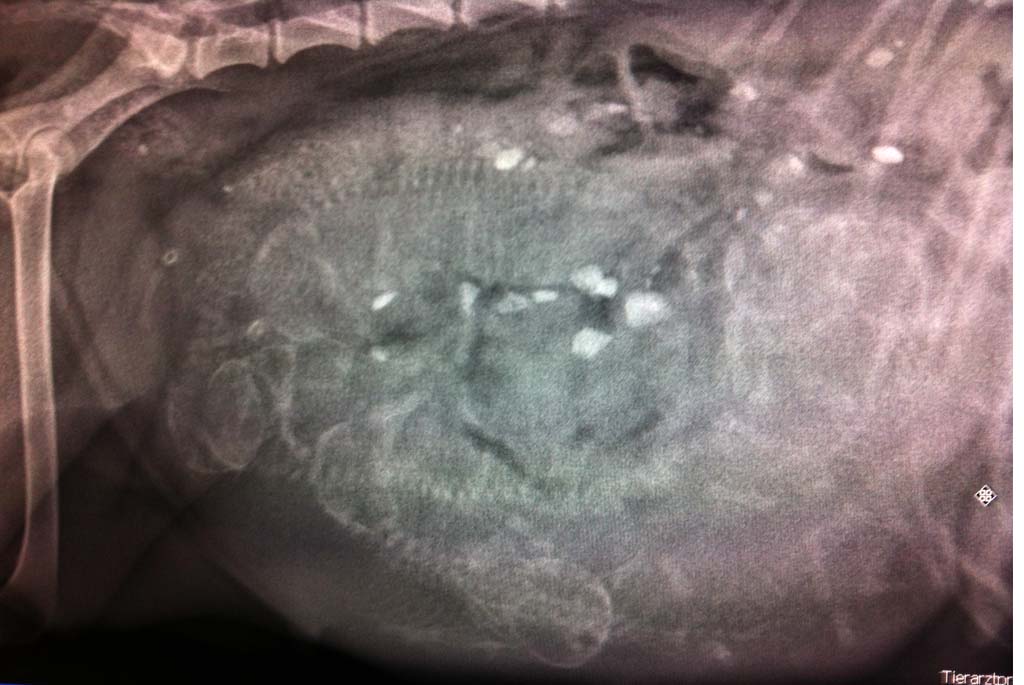

Inzwischen hat Sie beginnend vom ersten Tag ihrer Trächtigkeit eine Gewichtszunahme von 6kg (Stand heute Morgen). Dies in Kombination mit der Röntgenaufnahme lässt uns natürlich spekulieren ..... ;-)